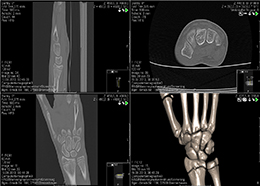

Bei der CT handelt es sich um ein röntgendiagnostisches computergesteuertes Verfahren. Bei der Untersuchung liegt der Patient auf einer beweglichen Liege, die innerhalb weniger Sekunden durch eine kurze Röhre fährt. In dieser wird er von einem Röntgenstrahler umkreist, wobei schichtweise Aufnahmen aus vielen Richtungen entstehen. Aus diesen ergibt sich bei modernen Multislice-Scannern ein dreidimensionaler Datensatz, der anschließend an einem Hochleistungscomputer durch den Radiologen ausgewertet wird.

Die CT wird bei diversen Erkrankungen zur Klärung von Organveränderungen, Blutungen und Flüssigkeitsansammlungen sowie auch bei Tumorverdacht durchgeführt. Auch Verengungen und Verkalkungen in den hirnversorgenden Gefässen, der Körperschlagader, den Herzkranzgefäßen oder Tumoren im Darm können heute mittels CT nachgewiesen werden. Hinsichtlich bestimmter Erkrankungen der Lunge und des Bauchraumes und hinsichtlich der Untersuchung von schwerkranken oder beatmeten Patienten gibt es derzeit häufig keine strahlungsfreien Alternativen. Die CT ist daher in vielen Fällen eine unverzichtbare radiologische Methode zur Erfassung krankhafter Veränderungen im menschlichen Körper, deren Nutzen das Strahlenrisiko bei weitem übertrifft.

Das IRNB setzt hochmoderne Multislice-Scanner mit bis zu 64 Zeilen ein.